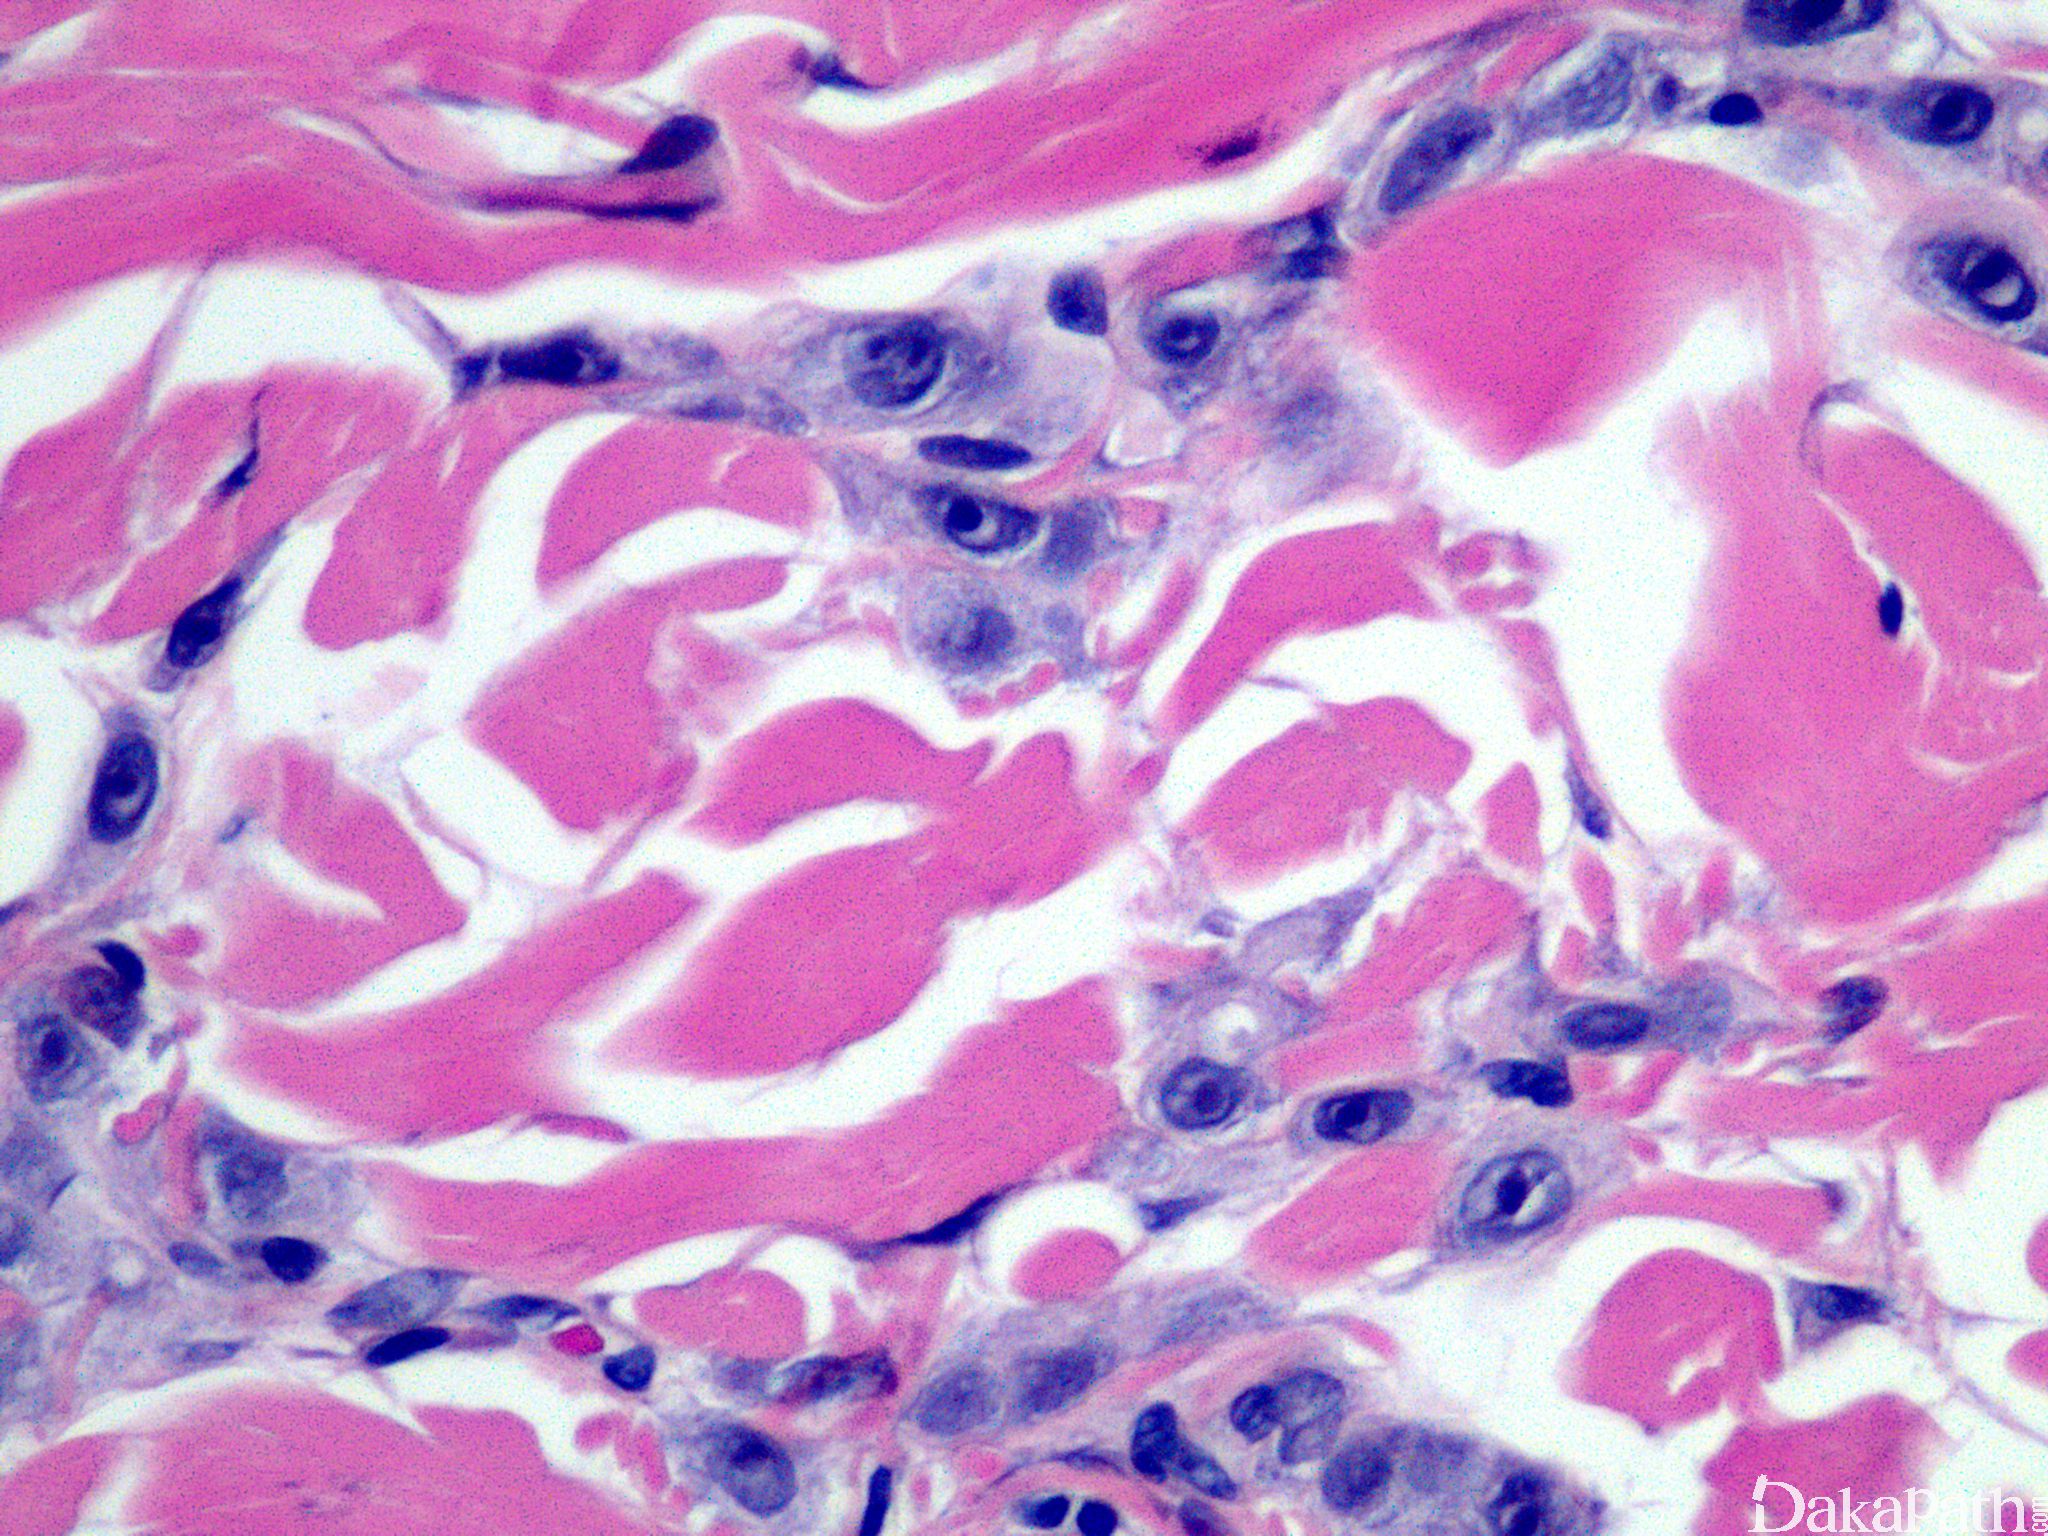

皮肤乳腺转移癌